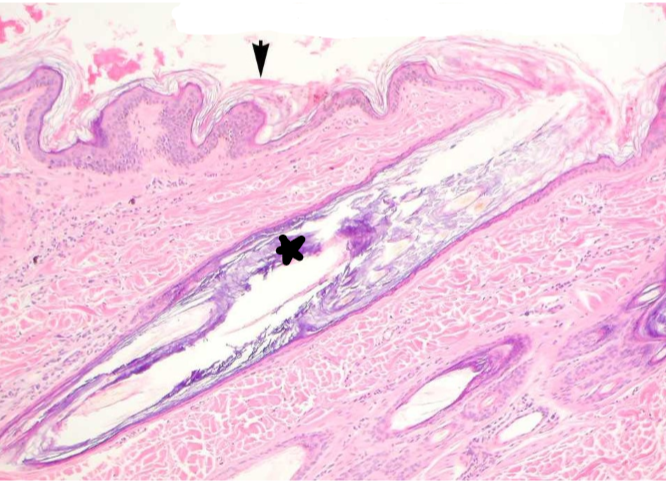

What is indicated by the arrow? The star? Is this change acute or chronic?

orthokeratotic hyperkeratosis (arrow);

There is so much keratin present that it has started to plug up the hair follicle (star);

Change is chronic